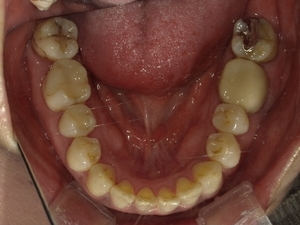

〇ご相談内容:上の前歯が内側に入っている、下の歯のがたつきが気になる〇矯正の種類:マウスピース型矯正「インビザライン」〇治療期間:14週間(約3ヵ月)〇治療費用:44万円(税込)